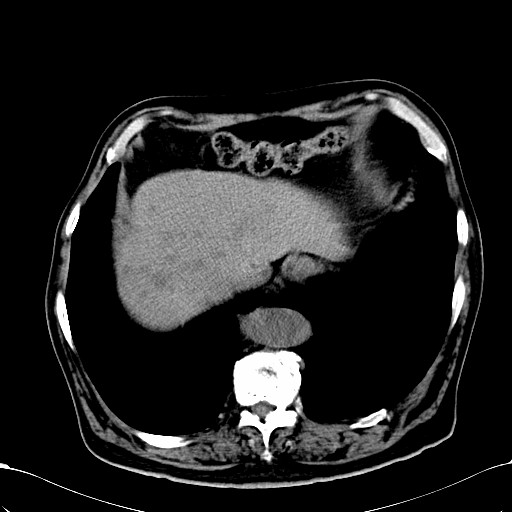

标题: CT28270:胰管扩张,肝多发占位 [打印本页]

标题: CT28270:胰管扩张,肝多发占位

患者,男,75岁。

肝脏多方低密度结节,边缘模糊,考虑多发转移,胰管明显扩张,建议增强扫描钩突情况

肝脏多发低密度灶,胰头似呈低密度,胰管扩张,建议增强,